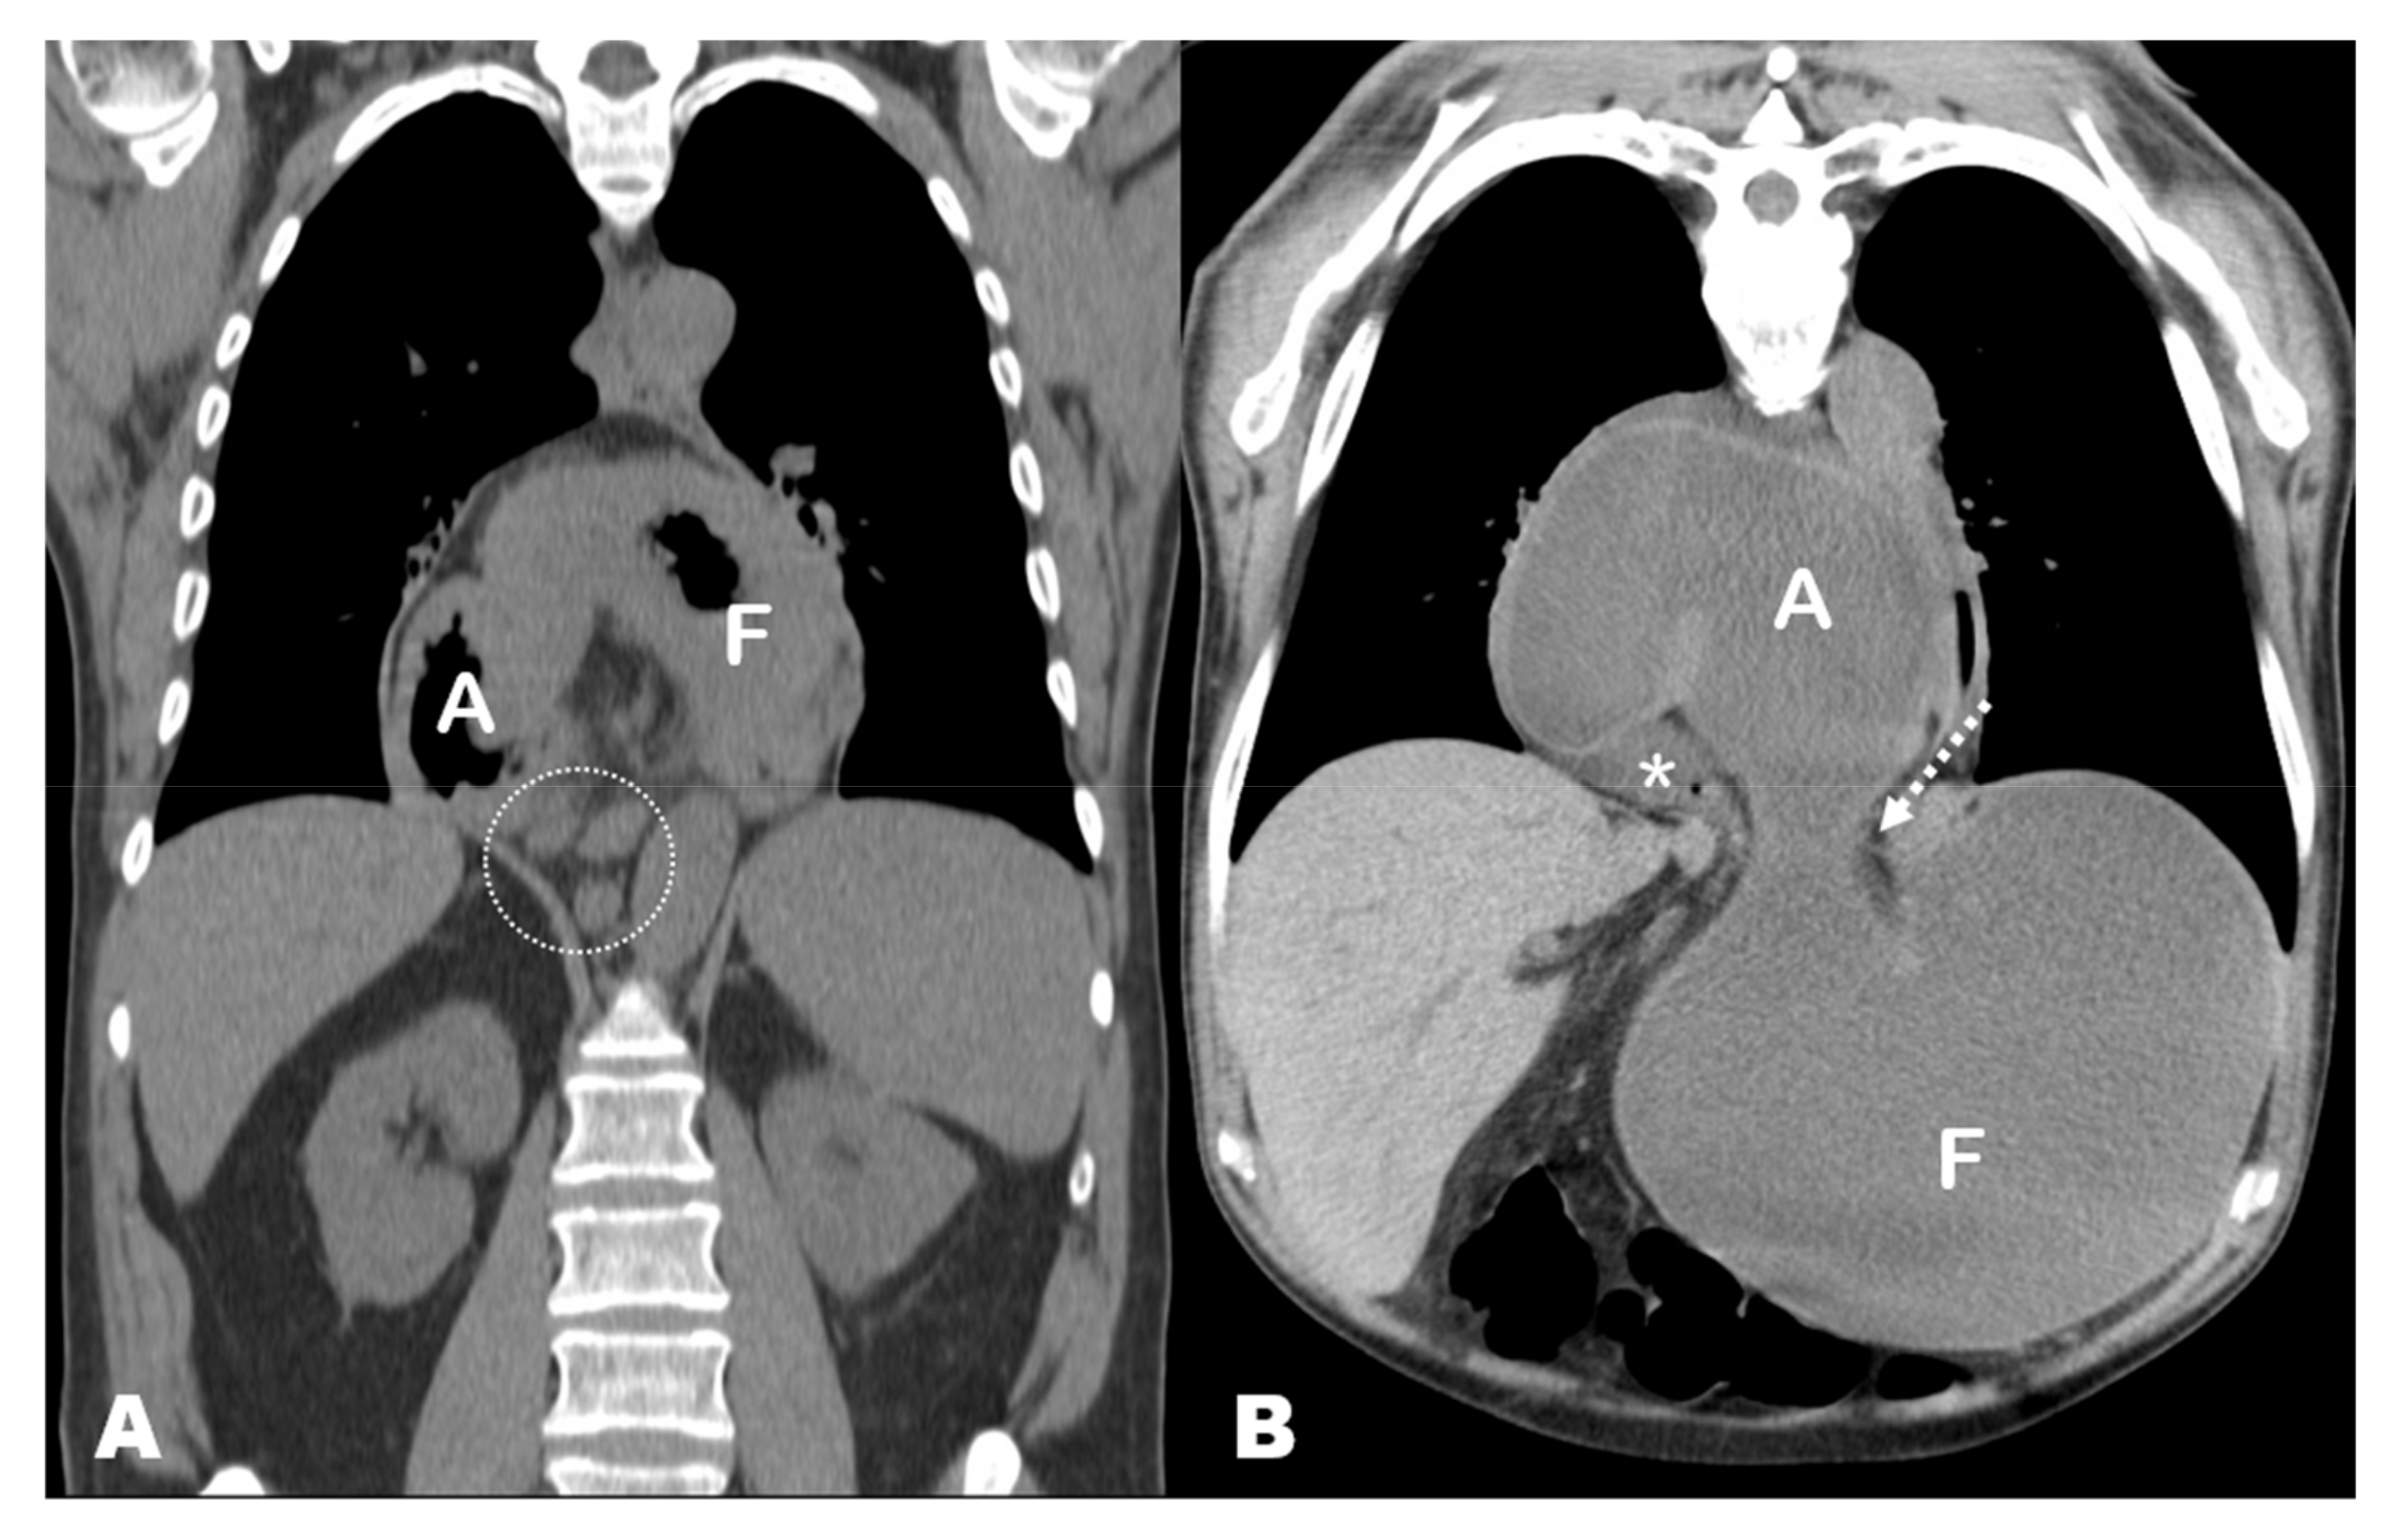

3. Results